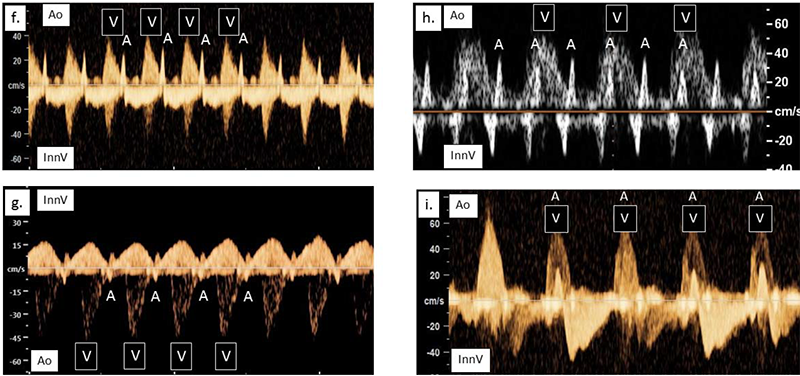

The InnV/Ao method provides a near 0-degree angle of insonation of the InnV to optimize visualization of the retrograde atrial systolic flow. (See Figure 2 for fetal arrhythmias detected with the method.)

Research conclusion: Our InnV/Ao Doppler technique is an acceptable modification of the SVC/AAo technique

Children's Colorado is the first to use simultaneous Doppler recordings of the InnV and Ao from an axial plane to assess fetal cardiac arrhythmias. The InnV/Ao Doppler technique is an accurate method to assess fetal heart rhythm and can be regularly performed in the clinical setting.